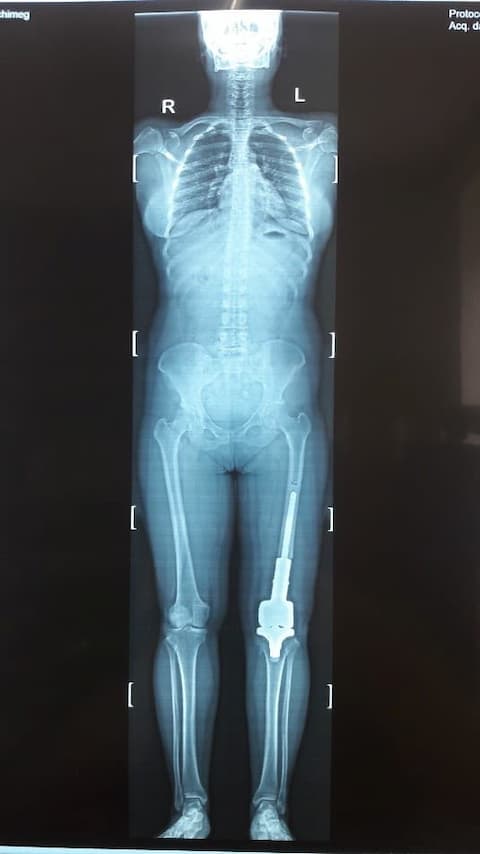

Үе дайрсан ясны анхдагч хавдар, ясны дутмагшлын үед хийгдэх мэс засалimage8Үе дайрсан ясны анхдагч хавдар, ясны дутмагшлын үед хийгдэх мэс засалimage9

Зураг 1. Гадна харагдах байдал: Зүүн дунд чөмөгний өвдөгний үе орчмын ясны хавдар, хавдар задар үхэжсэн байна.

Үе дайрсан ясны анхдагч хавдар, ясны дутмагшлын үед хийгдэх мэс засалimage10

А. Мэс засал хийсэн өвдөгний үе

Үе дайрсан ясны анхдагч хавдар, ясны дутмагшлын үед хийгдэх мэс засалimage11

Б. Бүтэн биеийн рентген зураг

Зураг 2. Мэс заслын дараах рентген зураг

Хавдрын улмаасмэс хийлгэсэнөвчтөнгүүд мэс заслын дараа 2-3 хоногийн дотор шууд гишгэж явж, мөчдийн үйл ажиллагаа хурдан сэргэж эхний 1 сард үений хөдөлгөөний далайц хэвийн болсон .